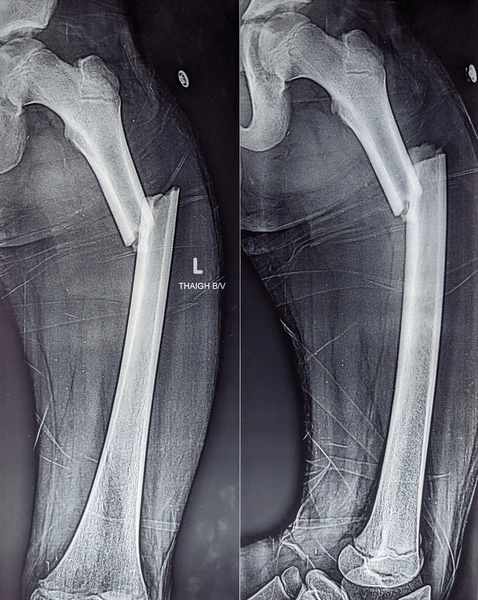

- Femoral shaft fracture – Break along the long, straight part of the bone

- X-rays to confirm the fracture and assess its type